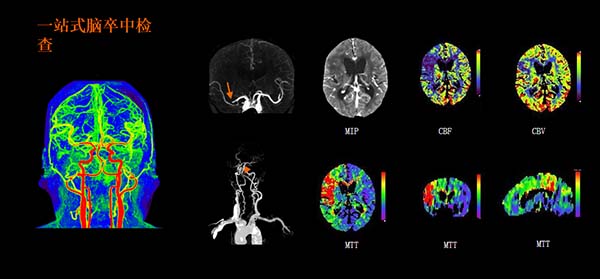

传统CT进行心脏冠脉成像时,常对患者心率有较高要求。而双源CT凭借其独特设计,可不受心率波动影响,轻松完成清晰的心脏冠脉成像,为冠心病等疾病的诊断提供了有力工具。同时,“一站式”胸痛三联征或脑卒中扫描也仅需约3秒,为急救争取宝贵时间。